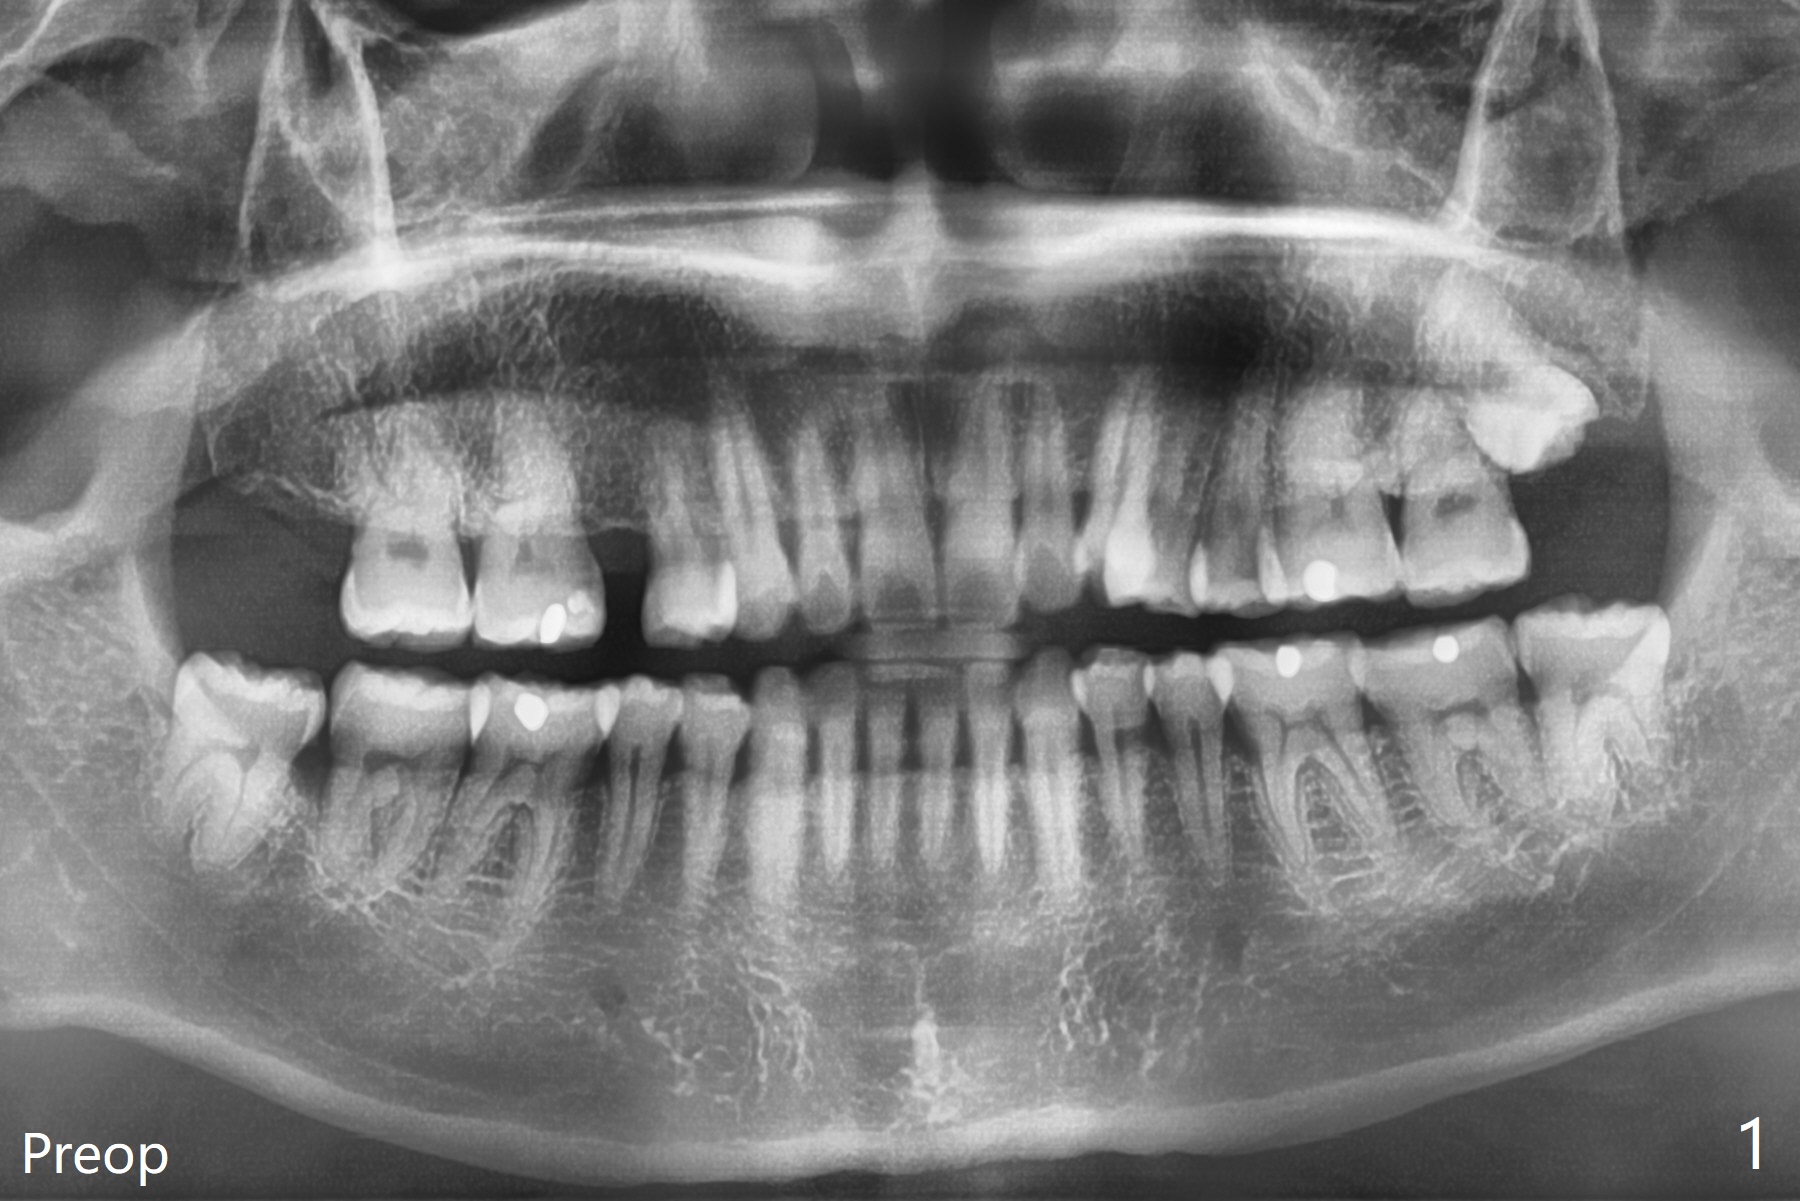

A 40-year-old man requests extraction of the teeth #17 and 32 (Fig.1). This case is designed to test that socket ossifies coronal when Collagen Plug is placed coronal. Release incision will be made both sides. Collagen plug will be placed at #32; none at #17. 4-0 PGA will be used to close the sockets. Photos will be taken immediate, 1 week, 1 month, and 3 months postop. PAs (sensor 1) will be taken immediate and 3 months postop. There is no wound dehiscence 1 week postop (Fig.6,7). The sockets reopen asymptomatic 3 weeks postop (Fig.8-11).